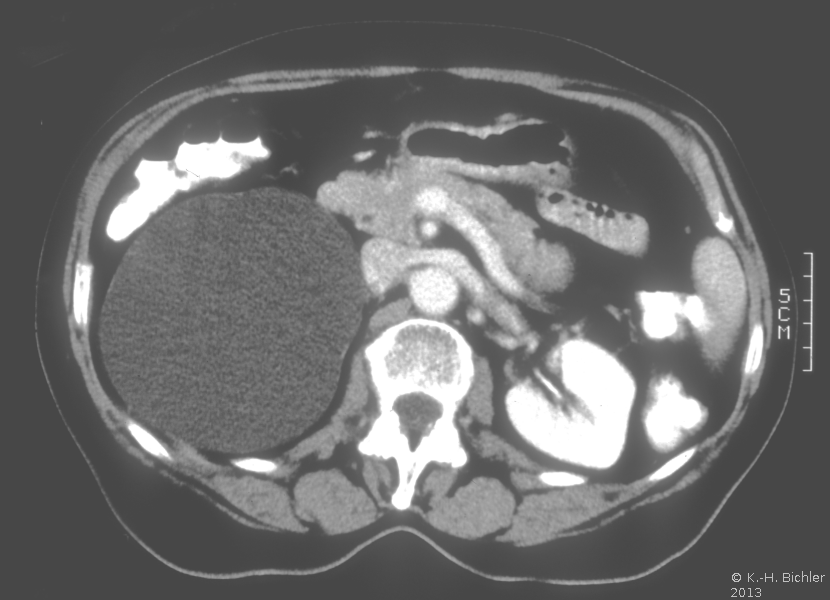

Die Patientin wurde beim Urologen wegen seit 3 Wochen persistierender Flankenschmerzen rechts vorstellig. Der Untersuchungsbefund zeigte als Auffälligkeit ein klopf- und druckschmerzhaftes Nierenlager rechts. Der Urinstatus wies keine Besonderheiten auf. Sonographisch fand der Urologe eine ca. 11 cm große einfache Nierenzyste rechts, die bis in das Nierenbecken reichte. Mit dem anschließend durchgeführten i.v.-Pyelogramm konnte eine Abflussbehinderung aus dem Nierenhohlraumsystem ausgeschlossen werden. Es waren jedoch glatt berandete, zystentypische Kelchausziehungen der oberen und mittleren Kelchgruppe zu erkennen. Der Urologe stellte die Patientin stationär in der Klinik vor. Zum Ausschluss eines eventuell vorliegenden zystischen Karzinoms wurde ein CT des Abdomens durchgeführt. Hier fand sich eine große, unkomplizierte Zyste, die die Niere verdrängte (Abbildung 4).

Zur Behandlung erfolgte die laparoskopische Nierenzystenfensterung. Die Patientin war danach beschwerdefrei. Ein Rezidiv trat nicht mehr auf.